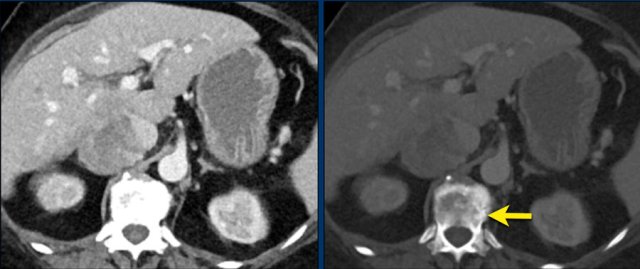

Axial venous phase CT in mediastinal and bone window setting Axial venous phase CT in mediastinal and bone window setting

Images depict mediastinal and bone window setting of a patient with a bulky heterogeneously enhancing right adrenal tumor.

This was proven to be an adrenocortical carcinoma.

There is a faint, ill-defined liver lesion in segment 6 and there are non-specific sclerotic changes in the body of T12.

Continue with the PET-image...

PET-CT performed for complete staging shows intense uptake in the adrenal tumor, indicative of its malignant nature.

There is also intense uptake in two liver metastases and in a bone metastasis in T12.

Approximately 20-40% of patients with an adrenocortical carcinoma present with metastases at diagnosis.